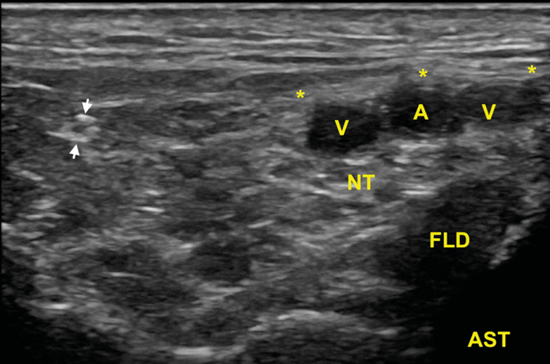

El nervio tibial, que se sitúa en superficie a las estructuras musculotendinosas y bajo la fascia crural, de forma habitual está dispuesto posterior a los vasos tibiales posteriores (Figura 6).

Figura 6. Túnel tibiocalcáneo. El examen en eje corto, bajo la fascia crural (*) y de anterior a posterior, muestra el tendón tibial posterior (TP), el tendón flexor largo de los dedos (FCD) aún con fibras musculares, y el músculo flexor largo del primer dedo (FLD). Entre estas dos estructuras se encuentra el haz neurovascular que está formado por las venas (V), la arteria (A) tibial posterior y por el nervio tibial (rodeado por X).

El nervio tibial tiene forma más o menos redondeada, patrón fibrilar con zonas punteadas anecogénicas e hiperecogénicas que corresponden a los haces nerviosos y al tejido conectivo de sostén, la típica imagen denominada de “sal y pimienta”, y sección transversal entre 10 mm26 y 12,7 mm27 a nivel del maléolo tibial (Figura 7).

Figura 7. Examen en eje corto del nervio tibial (x) posterior adyacente a los vasos tibiales posteriores.

Figura 9. En esta imagen en eje corto, la rama calcánea (flechas) una vez que ha atravesado las láminas de la fascia crural (*) y se ha ido separando del nervio tibial (NT) que se encuentra debajo de los vasos (A, V), y sobre el tendón flexor largo del primer dedo (FLD) y el astrágalo (AST).